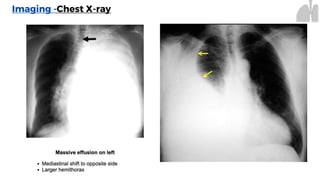

Imaging -Chest X-ray

Unilateral Pleural Effusion Bilateral Pleural Effusion

Supportive findings

⚬ Typically unilateral blunting of the

costophrenic angle

⚬ Homogeneous density with a meniscus-

shaped margin (meniscus sign)

• Large effusion

⚬ Complete opacification of the lung

⚬ Mediastinal shift

⚬ Tracheal deviation away from the effusion

(may be due to a space-occupying lesion)

Imaging -Chest X-ray Indications •Standard initial imaging modality for detecting pleural effusion. • Lateral decubitus view (most sensitive): allows for detection of fluid collections as small as 5mL Unilateral Pleural Effusion Bilateral Pleural Effusion Supportive findings ⚬ Typically unilateral blunting of the costophrenic angle ⚬ Homogeneous density with a meniscus- shaped margin (meniscus sign) • Large effusion ⚬ Complete opacification of the lung ⚬ Mediastinal shift ⚬ Tracheal deviation away from the effusion (may be due to a space-occupying lesion)